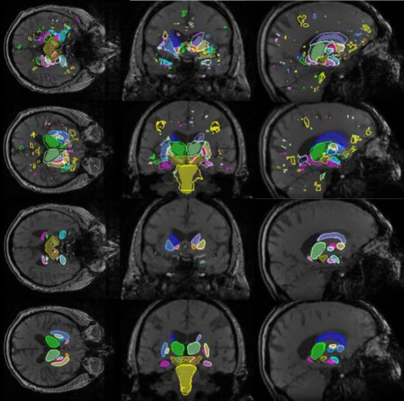

Visual examples of MRI segmentation results are visible in Figure. 4. It is notable that the Hough-CNN segmentation is able to correctly localise and segment multiple structures, despite large anatomical variability, such as cortical atrophy and enlarged lateral ventricles.

Our MRI dataset is composed of MRI volumes of subjects, which were acquired using 3D gradient-echo imaging (magnitude and phase) with an isotropic spatial resolution of 1x1x1 mm. The sequence [42] is designed for quantitative susceptibility mapping (QSM) and sensitivity towards iron deposits. These are biomarkers for movement disorders like Parkinson’s Disease and create visible contrast in relevant basal ganglia like SN and STN. For our study, basal ganglia and other deep-brain structures were annotated in an atlas volume in two ways. One set of bi-lateral atlas labels (brainstem, n. accumbens, amygdala, caudate, thalamus, hippocampus, pallidum, putamen) were annotated semi-automatically via a shape- and appearance-model segmentation (FSL FIRST [43]) plus manual correction of generated labels (one neuroimage technician, verified by one expert neurologist). Another set of bi-lateral labels (separation of of pallidus into GPi and GPe, midbrain, red nucleus, substantia nigra pars compacta and substantia nigra pars reticulata) was annotated in a fully manual manner (neuroimage technician, verified by expert neurologist) based on visible contrast. The atlas labels were transferred using a state-of-the-art atlas approach [44]. As a summary, the list of structures of interest is also visible in Figure 6.

In Figure 6 we compare the results achieved by the architecture “7-5-3”, on each of the 26 brain region of interest separately, when different data dimensionalities are used. The bar plot shows the results in terms of Dice coefficient, while the dashed line plot conveys the results in terms of average distance of the estimated contour to ground-truth delineation. We observe that Hough-CNN yields better Dice coefficients when bigger regions and high contrast area are segmented. Small and low contrast regions could be correctly localised but they were in general harder to segment.